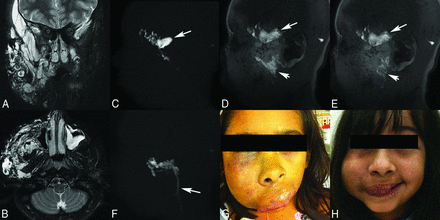

A 10-year-old girl with a very large venous malformation of the right face, who has had >20 previous treatment episodes with traditional digital subtraction angiography guidance, now being treated with MR imaging guidance. These images demonstrate the necessity of angiography to assure proper needle positioning. Coronal (A) and axial (B) T2-weighted fat-saturated MR images show the very large venous vascular malformation extending essentially throughout all superficial and deep spaces of the right face, producing significant local mass effect. C, Pretreatment MR angiogram, initial needle placement, demonstrates opacification of the venous malformation but also a focus of stagnation of contrast material that remained on the late-phase images, indicating extravasation (arrow). Thus, this is not a safe location to treat, and sclerotherapy was not performed. Note that normal venous backflow from the needle hub was initially detected, but adequate needle placement can only be assured following angiography. Early (D) and late (E) phase pretreatment MR angiograms, second needle placement, again demonstrate opacification of the venous malformation but now also show runoff of the contrast material on the late-phase image, indicating safe needle placement for embolization (arrowheads). Note the continued presence of the previously extravasated contrast material from the first injection on this nonmask subtracted image (arrows). F, Early-phase pretreatment MR angiogram, third needle placement, depicts needle localization within the venous malformation; however, there is very rapid filling of an enlarged draining vein (arrow). Thus, this is not a safe location to treat, and sclerotherapy was not performed. Again, adequate needle placement can only be assured following angiographic visualization of the lesion. Patient photographs before (G) and following (H) MR sclerotherapy show significant improvement in right facial swelling; however, a persistent right facial venous malformation is still present, requiring additional multiple future treatment sessions.